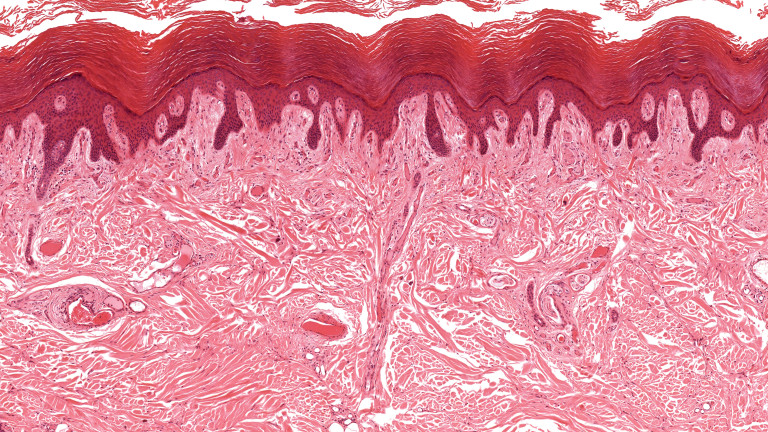

„Новият” орган интерстициум и какво трябва да знаем за него

Опознаваме тялото си все по-добре